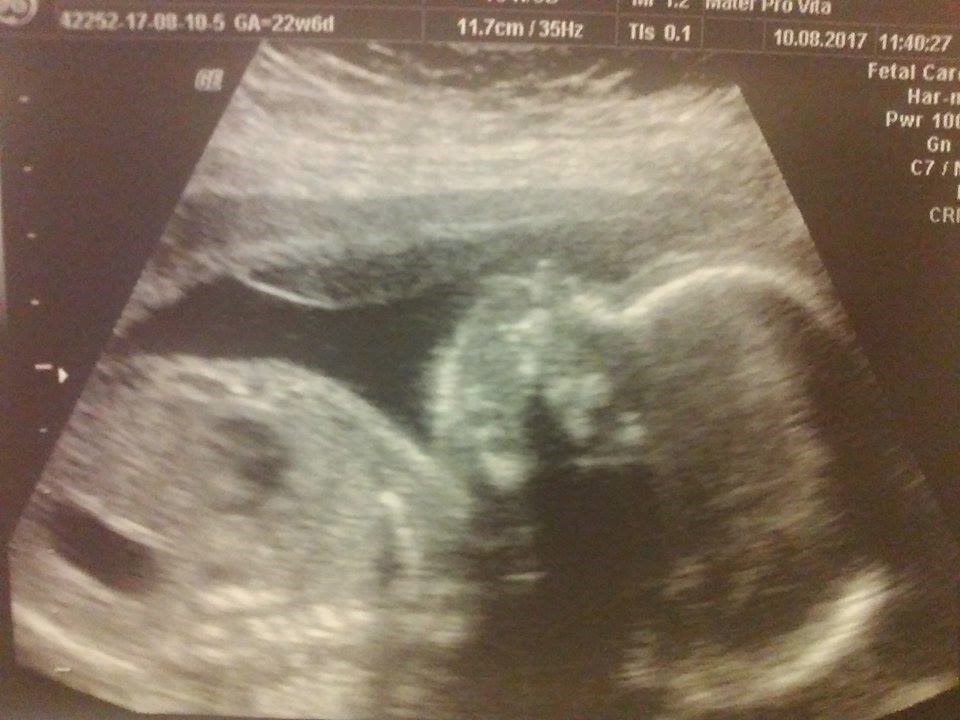

Na połówkowych wszystko dobrze, kręgosłup pani dr bardzo dokładnie przejrzała (ze względu na moją wrodzoną wadę) i jak na razie nic nie widać by miało coś się dziać ale mam jeszcze sprawdzić po urodzeniu dla pewności. Mały dziś jak nigdy większość usg współpracował, aż go pani gin pochwaliła.

Pod koniec zaczął się coś odwracać ale stwierdziła że jak wtedy współpracował i szybko poszło, to teraz poczekamy sobie na niego i wtedy jak zaczarowany poszedł dalej na współpracę. Serducho też ślicznie pokazywał bo chyba spał podczas jego badania, 146 ud/min.

Ogólnie duży maluch mi rośnie bo już 640g, czyli od zeszłej środy +120g wyszło.

Zobacz załącznik 818270